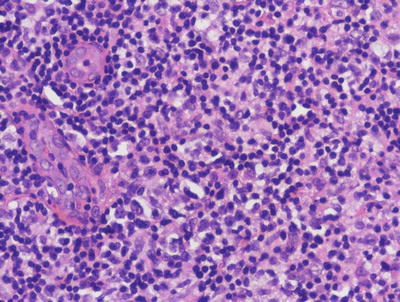

22.7.2 Histology

The cutaneous lesions in Rosai-Dorfman disease are histologically quite similar to changes described in the more common lymph node-based sinus histiocytosis with massive lymphadenopathy. A dense infiltrate of inflammatory cells fills much of the dermis with no tendency for invasion of the epidermis or cutaneous appendages [55, 56] (Figs. 22.16 and 22.17). Admixed with sheets of histiocytes are lymphocytes, neutrophils, plasma cells, and occasional eosinophils [57]. The histiocytes resemble those seen in lymph node sinuses and demonstrate emperipolesis, in which histiocytes engulf other inflammatory cells [58, 59]. While this finding is not pathognomic for the disease, it is a very characteristic finding in this entity, and is usually readily apparent on H&E staining. Plasma cells are often found rimming blood vessels within the midst of the lesions. Thick-walled vessels and lymphoid nodules have been described at the periphery of lesions [55].

Fig. 22.17

Large histiocytes may demonstrate emperipolesis, and may be surrounded by a dense collection of lymphocytes with occasional plasma cells and eosinophils in sinus histiocytosis with massive lymphadenopathy. Endothelial cells in dermal vessels are edematous and resemble small granulomas